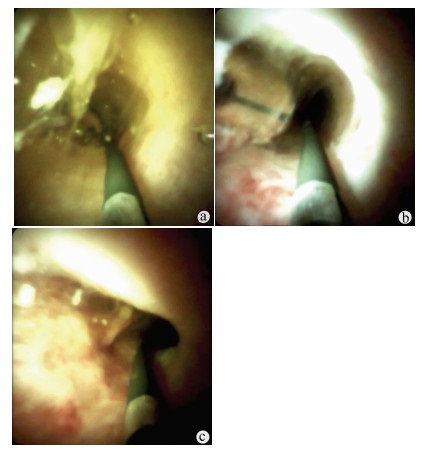

Endoscopic retrograde cholangiopancreatography combined with Spyglass in diagnosis of common bile duct papillary myxoma: A case report

Xuan DING, Linheng WANG, Gui JIANG, Yifei YUN, Xinyu LU, Yupu YAO

2021, 37(12): 2902-2904. DOI: 10.3969/j.issn.1001-5256.2021.12.034

Abstract(1315) HTML (221) PDF (2331KB)(47)

Abstract: